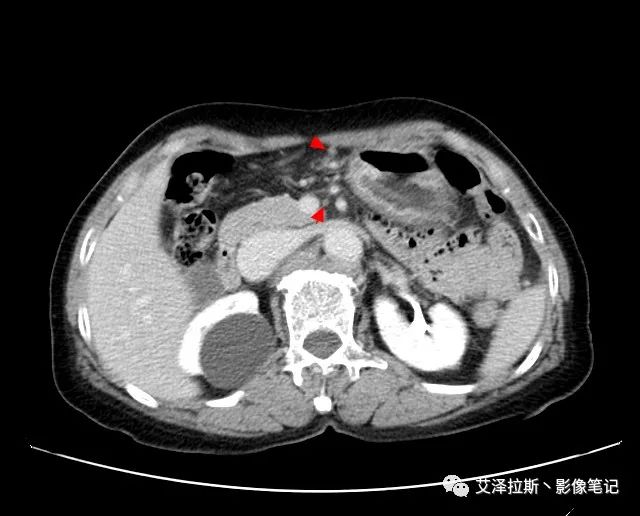

以下為累及的區域淋巴結,共計15個區域:

【影像所見】 胃竇部狹窄,胃壁環形增厚,小彎側見一巨大潰瘍,周圍伴“環堤征”,漿膜面不完整,胃周脂肪見網格狀條索影,病灶與肝臟左葉、胰腺鉤突脂肪間隙消失,增強掃描病灶明顯強化。引流區內約15個區域淋巴結受累。

【診斷意見】 胃竇部胃癌(T4N3期) 該病例腫塊突破漿膜層,與肝臟左葉、胰腺鉤突分界不清,脂肪界面消失,定為T4期; 受累及的淋巴結為15個區域,定為N3; 有無遠處轉移尚不明確,所以M期暫時無法確定。